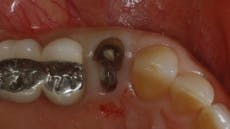

In the example shown in the photos, a patient presented with a severely broken down maxillary right first premolar tooth (No. 5) (Figure 2). Utilizing the Physics Forceps (Golden Dental Solutions), we atraumatically extracted the bifurcated remainder of this tooth (Figure 3) and curetted the socket. Once cleaned, bone grafting material (Foundation, J. Morita or Bioplant, Kerr Dental) was placed into the socket and sutured (Figure 4) to prevent any dislodgement.

Fig. 2 — Nonrestorable tooth (4138)